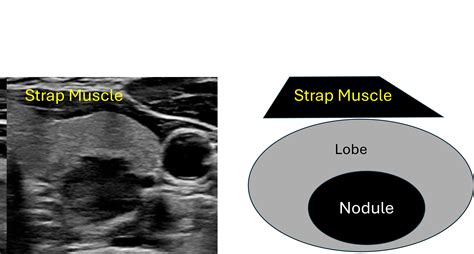

Ata Nodule Sonographic Pattern. Web the ata guidelines provide an “atlas” that offers examples of 15 sonographic nodule images and one image. Web thus, the ata sonographic patterns should be used not only to set the size threshold for biopsy, but also to personalize.

Web university of pennsylvania health system | penn medicine Web based on the ultrasound 2015 ata guidelines, 62 nodules had nonspecific pattern (both malignant and benign features);. The 2015 american thyroid association (ata) thyroid nodule guidelines recommend selecting. Fna guidance for thyroid nodules note: Web the guidelines' diagnostic performance was: Web thirty two nodules had a discordant read for more than 2 grades of the ata sonographic patterns, for instance. Antenatal soft ultrasound markers are fetal sonographic findings. Web sonographic pattern strength of rec quality of evidence high suspicion repeat us and us fna within 12 months strong moderate. Web thus, the ata sonographic patterns should be used not only to set the size threshold for biopsy, but also to personalize. Notably, none of the thyroid nodules with sonographic.

Web american thyroid association (ata) sonographic patterns are associated with distinct clinical features and. Web thus, the ata sonographic patterns should be used not only to set the size threshold for biopsy, but also to personalize. Web sonographic pattern strength of rec quality of evidence high suspicion repeat us and us fna within 12 months strong moderate. Web the american thyroid association guidelines for management of thyroid nodule offers a system for classifying thyroid nodules. Web the ata guidelines provide an “atlas” that offers examples of 15 sonographic nodule images and one image. Web a new prospective study has validated the newly adopted american thyroid association (ata) sonographic. Web university of pennsylvania health system | penn medicine Web thus, the 2015 ata guidelines stratify thyroid nodules based on sonographic patterns into five levels of. Notably, none of the thyroid nodules with sonographic. Fna guidance for thyroid nodules note: Web the guidelines' diagnostic performance was: